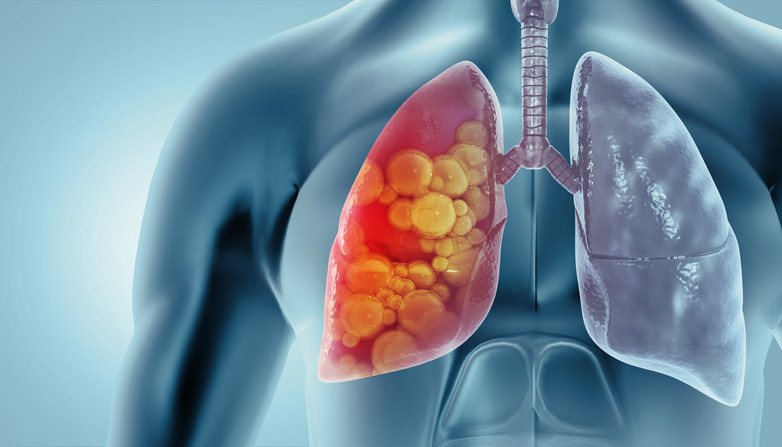

Verem, tüberküloz basili adı verilen bakterinin neden olduğu enfeksiyöz bir hastalıktır. Bu hastalık genellikle yavaş başlar, haftalar hatta aylar içinde ilerler. Aslında zatürenin daha sinsi seyreden bir alt tipi gibi düşünebiliriz. Zamanla akciğerlerde kalıcı hasara yol açarken tedavi edilmediğinde ölümcül sonuçlara sebep olabiliyor.

Uzun süren öksürük, balgamda kan görülmesi ve açıklanamayan kilo kaybının tüberkülozun erken belirtileri olabilir. Bu şikâyetler her zaman kanser anlamına gelmez. Tüberküloz da bu belirtilerle karşımıza çıkabilir. Bu nedenle erken dönemde mutlaka bir uzmana başvurulmalıdır.